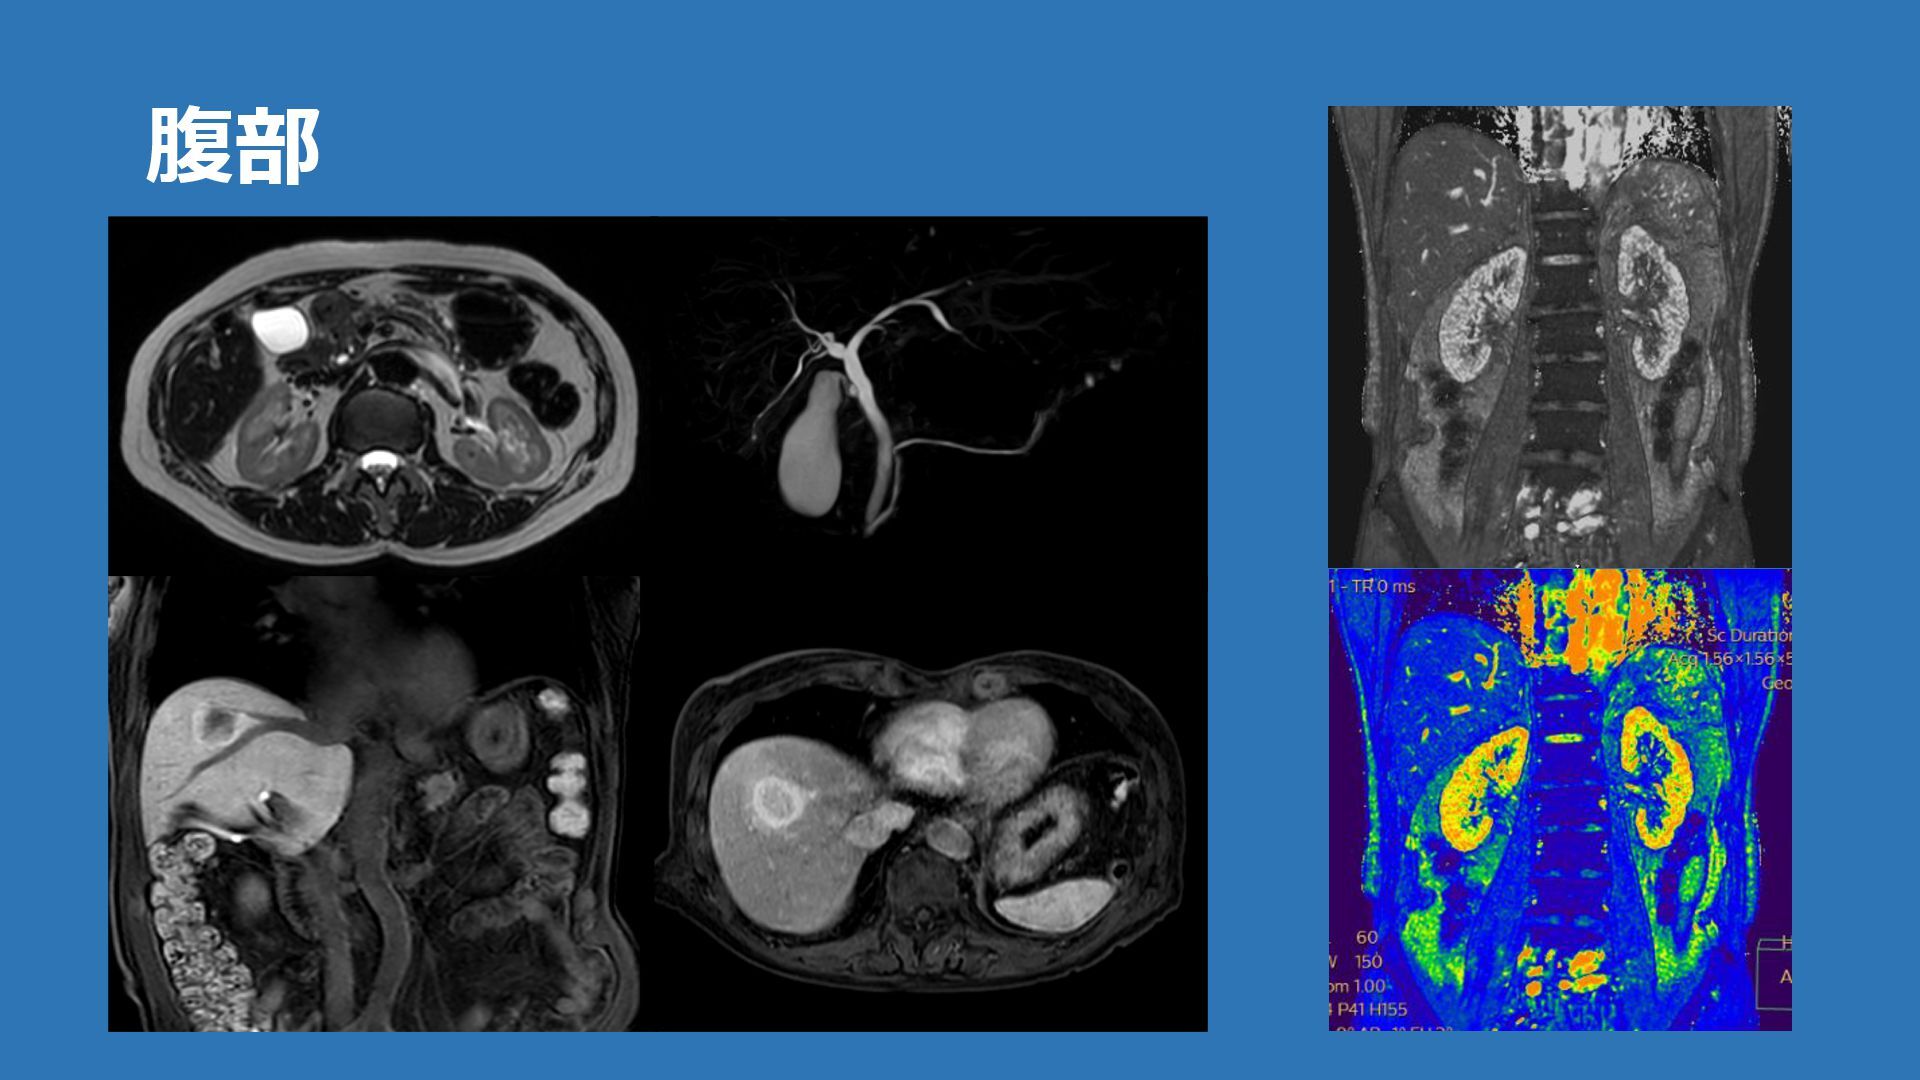

腹部